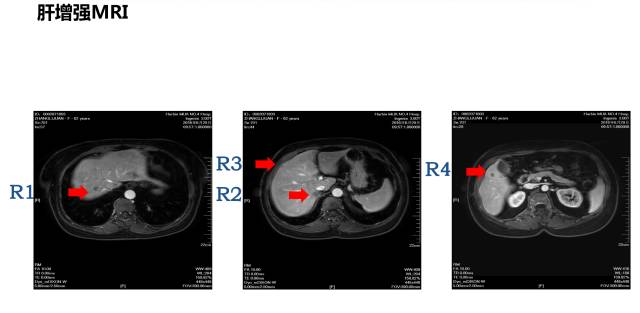

病理:盲肠腺癌肝脏MRI:共8枚病灶

1 2 肝转移病灶

3 右半结肠肿瘤